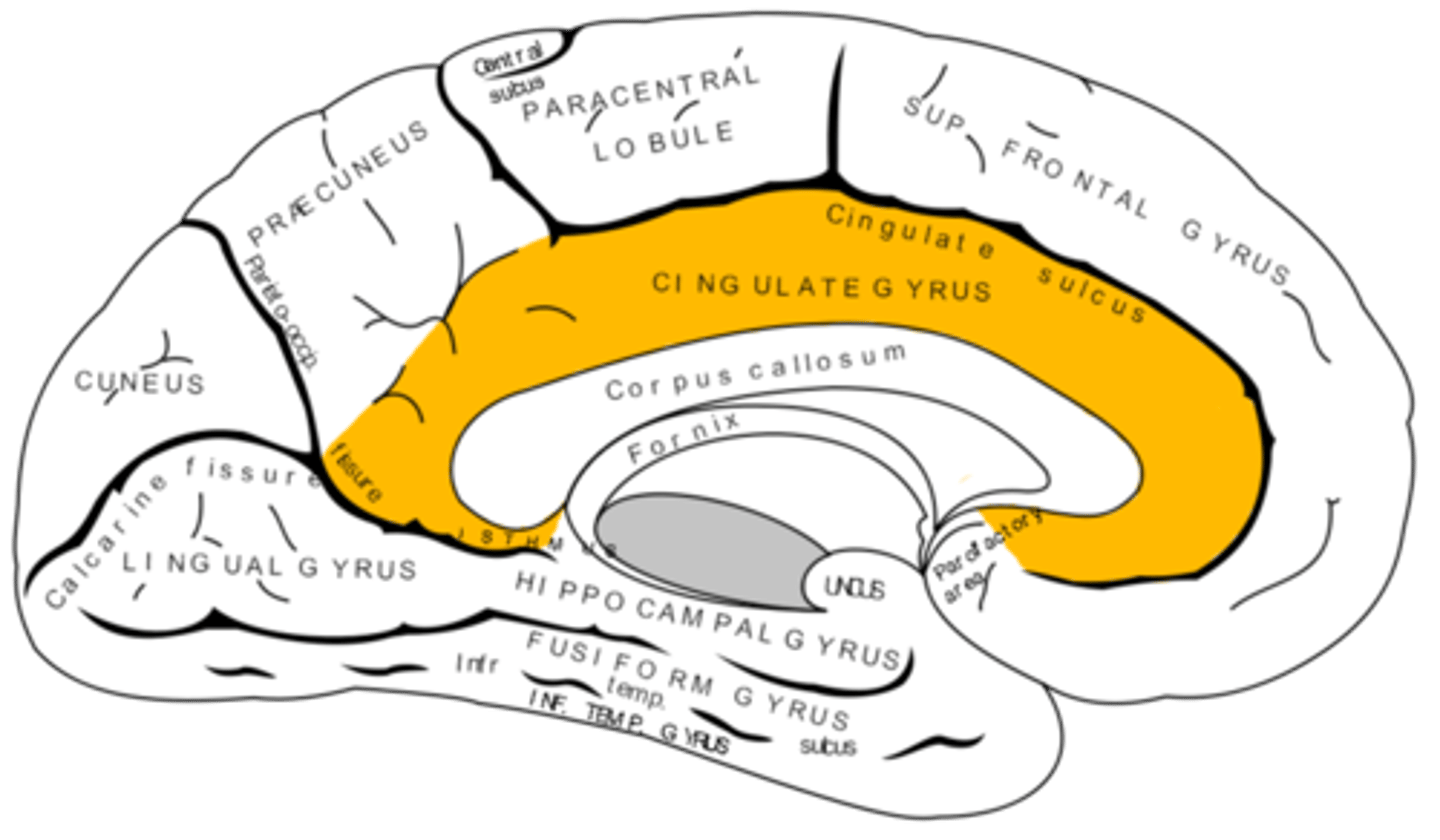

Where does the cingulate gyrus run?

superior to the corpus callosum

hippocampus via the cingulum

What is afferent to the anterior nuclei of the thalamus?

hippocampus and hypothalamus via mammillothalamic tract

What is the pathway from the hippocampus to the anterior nuclei of the thalamus?

1. hippocampus

2. fornix

3. mammillary nuclei

4. mammillothalamic tract

5. anterior nuclei (thalamus)